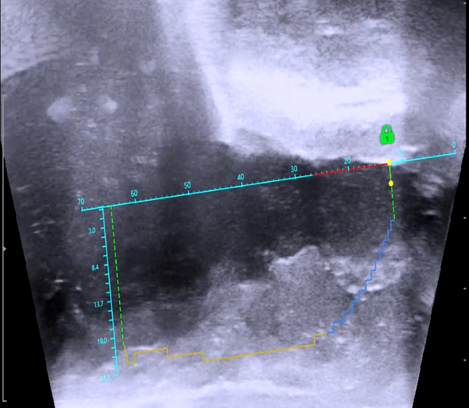

수술 전 막혀있는 전립선 초음파 소견

수술 후 잘 열린 전립선 초음파 소견